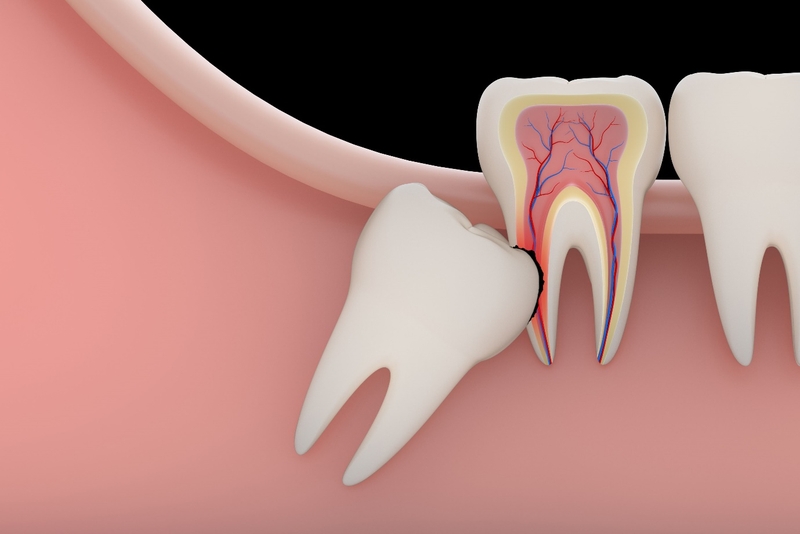

Trường hợp xấu hơn có thể lây lan sang các răng bên cạnh gây tiêu xương, lung lay...Nhiều trường hợp răng 8 mọc lệch, mọc ngầm dẫn đến tình trạng xô lệch các răng bên cạnh thậm chí là xô lệch cả hàm. Vì vậy đa số các trường hợp, các bác sĩ thường tư vấn nhổ răng khôn hoàn toàn.

Nhổ 2 răng khôn cùng lúc có nguy hiểm không? 2 Nếu không được xử lý răng khôn có thể gây nhiều nguy hiểm cho người bệnh

Ngoài ra, khi răng khôn mọc ngầm kẹt trong xương gây đau thì việc nhổ bỏ chúng cùng lúc giúp bệnh nhân giảm khoảng thời gian chịu đau. Nhổ 2 răng khôn cùng lúc cũng rút ngắn thời gian lành thương, bệnh nhân chỉ cần uống thuốc một lần thay vì mất đến 2 lần. Vì thế mà nhổ 2 răng cùng lúc vẫn lợi hơn nhổ từng răng một.

Nhổ 2 răng khôn cùng lúc có nguy hiểm không? 3 Răng khôn kẹt trong xương gây đau đớn cho người bệnh